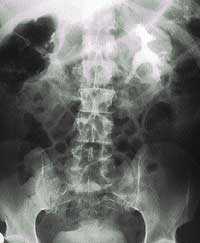

- Рентгенография . Выявляет структурные аномалии мочевыводящих путей, такие как сужение мочеиспускательного канала и неполное опорожнение мочевого пузыря.